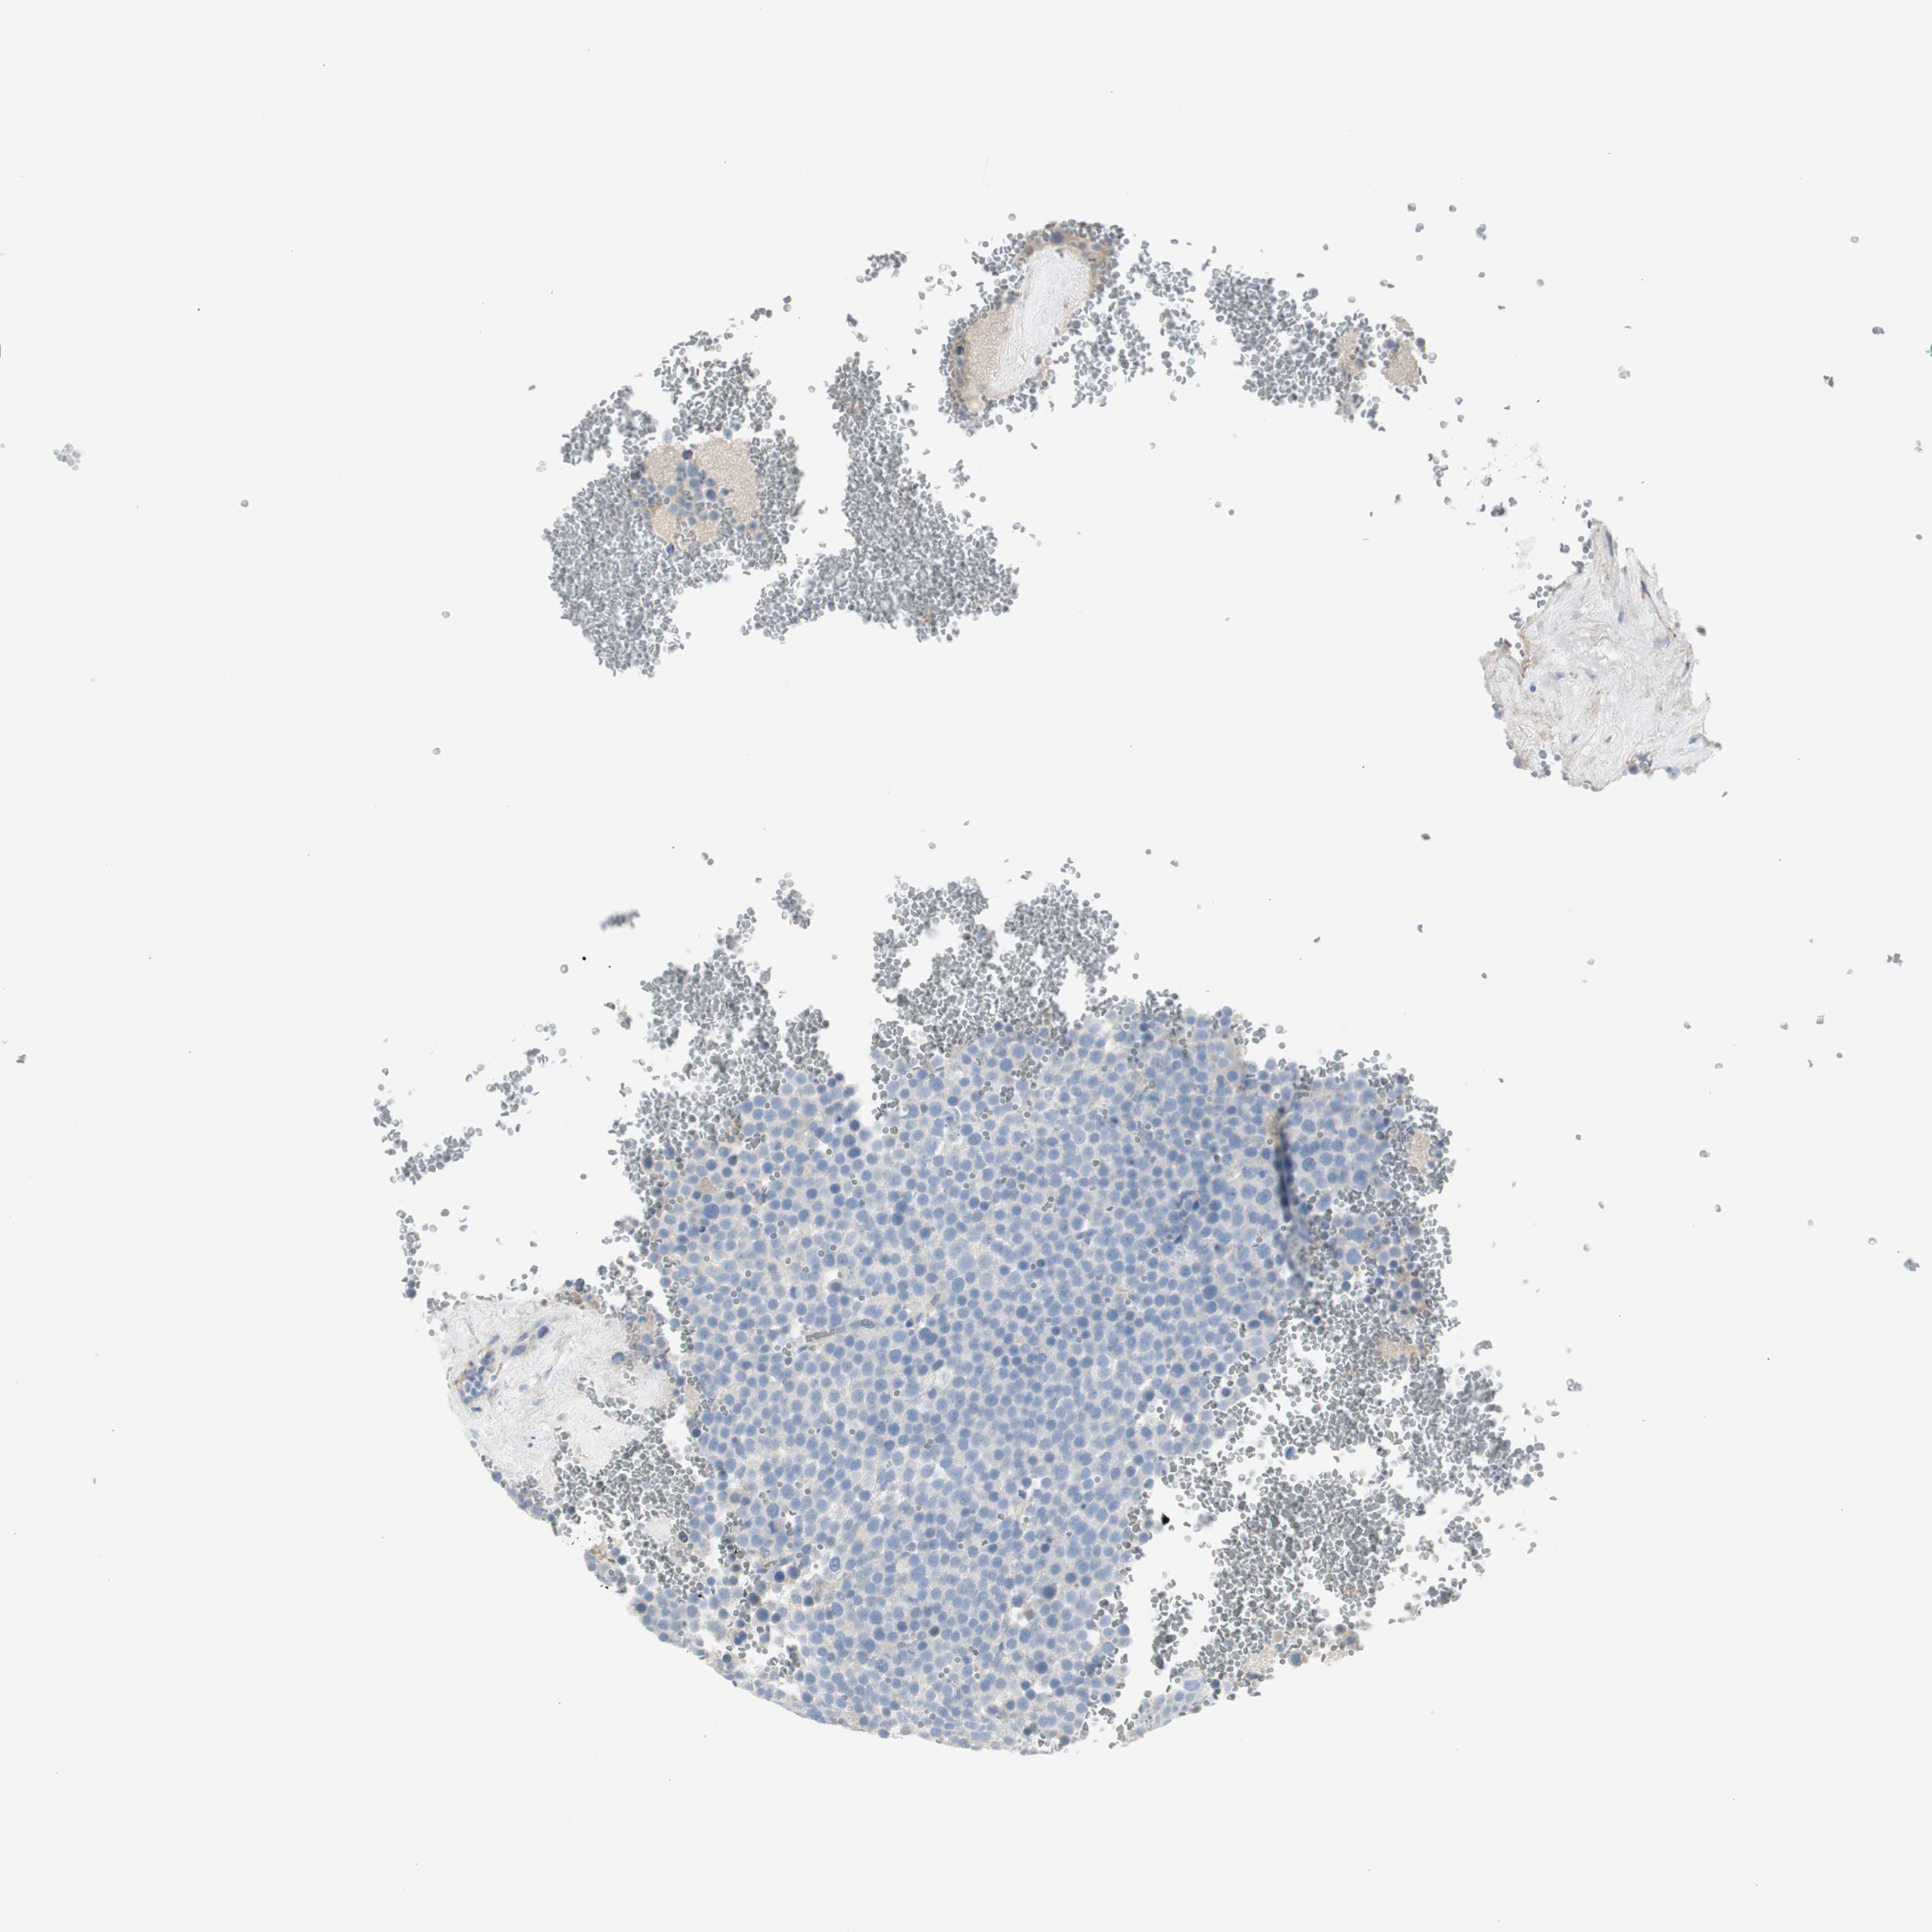

TESTIS CANCER - Protein expressioni

A mouse-over function shows sample information and annotation data. Click on an image to view it in a full screen mode. Samples can be filtered based on level of antibody staining by selecting one or several of the following categories: high, medium, low and not detected. The assay and annotation is described here.

Note that samples used for immunohistochemistry by the Human Protein Atlas do not correspond to samples in the TCGA dataset.

Antibody stainingi

Antibody staining in the annotated cell types in the current human tissue is reported as not detected, low, medium, or high, based on conventional immunohistochemistry profiling in selected tissues. This score is based on the combination of the staining intensity and fraction of stained cells.

Each image is clickable and will lead to virtual microscopy that enables deeper exploration of all samples and also displays staining intensity scores, fraction scores and subcellular localization as well as patient and tissue information for each sample.

Antibody HPA008213

Antibody HPA008621

Staining

High

Medium

Low

Not detected

Intensity

Strong

Moderate

Weak

Negative

Quantity

>75%

75%-25%

<25%

None

Location

Nuclear

Cytoplasmic/membranous

Cytoplasmic/membranous,nuclear

Carcinoma, Embryonal, NOS

Seminoma, NOS